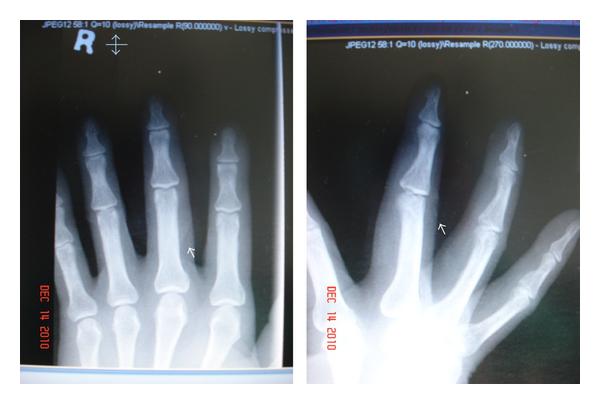

A healthy 57-year-old, male, Chinese with a good past medical health, right hand dominant worked as maintenance worker in a company. While working, a lamp metal bar cover fell on the right middle finger which causes laceration. Upon examination at the Accident and Emergency Department, bleeding wound further had examination under digital block anaesthesia with lacerated wound 3 cm obliquely at the posteroradial aspect of the proximal phalanx and 80% cut of the extensor tendon and no bony involvement. Radiograph findings revealed no bony involvement (Figure 1).

Following trauma and surgical procedure, extensive physiotherapy rehabilitation programme and occupational therapy treatment protocol was implemented. After the removal of skin sutures, a palpable mass was noted that begins as a painful over the scar which gradually becomes nontender and gradually increases, as well as firmer to palpation in progressive increase in size at the 19th day after the surgery with continuous extensor programme rehabilitation, and it develops gradual decrease of the range of motion on the metacarpal phalangeal joint as well as the proximal interphalangeal joint even with standard rehabilitation programme; later on, it develop into significant block of flexion and extension (Figure 2). Radiographic imaging taken with calcifications was noted (Figure 3).